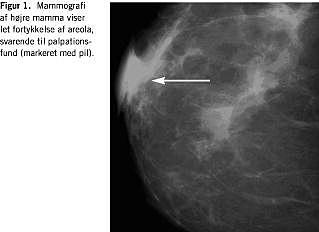

Parakliniske undersøgelser: En mammografi viste let fortykkelse af areola i overensstemmelse med palpationsfundet. (Figur 1 ). Forandringerne var derimod ikke synlige på den samtidigt foretagne ultralydscanning. Processen blev biopteret med stansebiopsi. En histologisk undersøgelse viste pseudolymfom, og på anbefaling fra patologisk afdeling blev der foretaget måling af Borrelia -antistof. Der påvistes en forhøjet Borrelia burgdorferi- antistof IgG-titer på 497 (ref. < 6 U pr. ml), og patienten påbegyndte behandling med tablet phenoxymethylpenicillin 1,5 MIE × 3 i ti dage. Ved klinisk kontrol på Brystkirurgisk Klinik seks uger senere målte den skiveformede fortætning 8 mm × 8 mm × 2 mm og var således formindsket til en tredjedel af den oprindelige diameter. Der fandtes ikke indikation for kirurgisk intervention. Ved afsluttende kontrol en måned efter penicillinbehandlingen, kunne processen ikke genfindes.

Da den Borrelia- betingede tumor i denne kasuistik alene kunne erkendes visuelt på mammografi, kan det måske i udvalgte tilfælde være nødvendigt at supplere med mammografiundersøgelse hos en yngre kvinde med en retroareolær tumor. Mammografi som primærundersøgelse betragtes dog almindeligvis ikke som indiceret hos kvinder under 30 år. Yderligere er en omhyggelig anamnese vigtig.